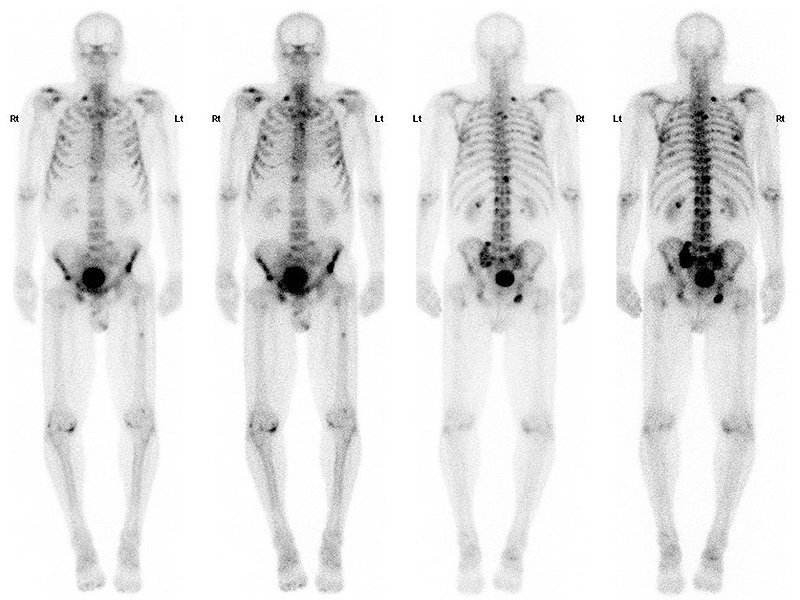

How is a bone scan done + how does it work?

Technetium injected Excreted by kidneys Osteoblasts take up tracer

What does a bone scan show?

Tracer goes to site of increase bone remodelling (sclerotic bone mets, healing fractures, osteomyelitis)

What are the consequences of bone mets + how are they diagnosed?

Marrow involvement = increased fracture risk, anaemia + spinal cord compression

Bone scan

What are the types of bone mets + what cancers cause each type?

Lytic (kidney, lung cancer) Sclerotic (prostate)